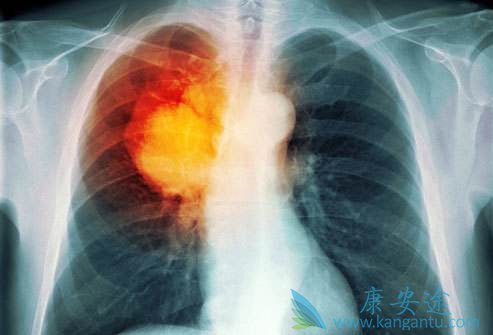

肺癌脑转移分为脑实质转移和脑膜转移

脑转移分为脑实质转移和脑膜转移。实质转移最常见部位为大脑半球,随后依次为小脑、脑干。脑膜转移少见,预后更差。肺癌脑转移发生率较其他恶性肿瘤高,约20-65%的患者会在病程中出现。SEER数据称,非转移性腺癌、鳞癌、大细胞癌脑转移发生风险分别为11%、6%、12%。小细胞肺癌首诊时发病率即为10%,存活2年以上患者发生率达60-80%。

肺癌脑转移

MRI为首选,平扫可见T1中低、T2中高信号,周围水肿。增强扫描可见明显强化。CT多为等密度、低密度,少数高密度;典型病灶强化明显,周围水肿。肿瘤组织呈高摄取,有助于寻找原发灶。但是小脑转移灶摄取不明显。腰穿完善脑脊液常规、生化、细胞学、病理等检查有助于明确诊断。尤其软脑膜转移患者可出现脑脊液压力增高、蛋白含量增高。

肺癌脑转移需全身治疗基础上综合诊治。包括手术、全脑放疗(WBRT)、立体定向放疗(SBRT)、化疗、靶向药物治疗等。有症状应积极局部治疗。脑转移瘤不超过3个可行手术/SBRT/SBRT联合WBRT治疗。多于3个应行WBRT或SBRT治疗。